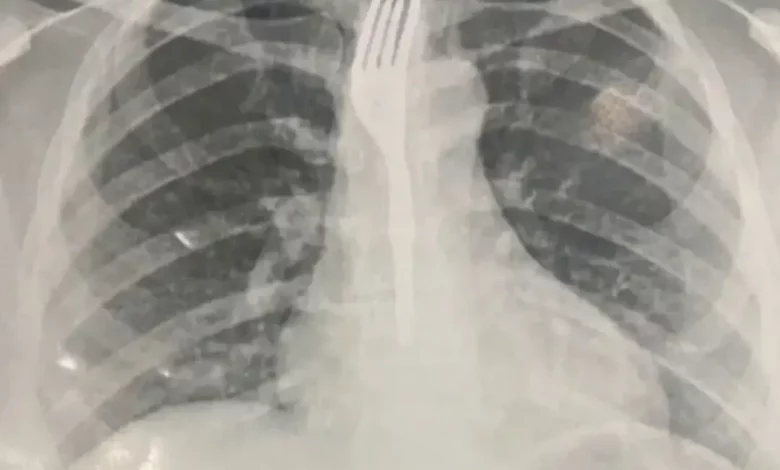

A vítima foi atendida no Hospital Geral de Guanambi (HGG), onde exames de imagem revelaram que o utensílio estava preso no esôfago, em posição de risco. Devido à gravidade do caso, a paciente foi transferida para Vitória da Conquista, onde passará por procedimento especializado para a remoção do garfo.